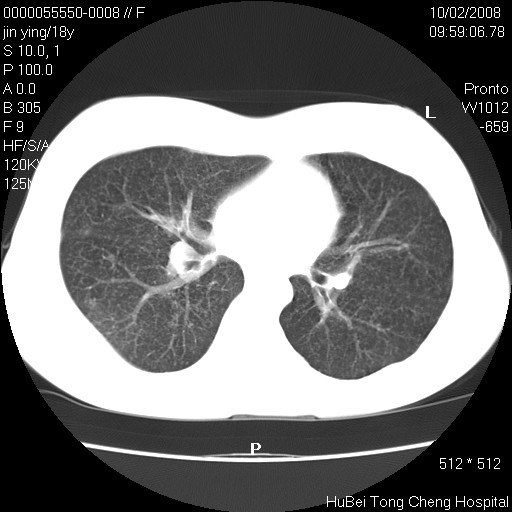

患者 女,18y。发热十余天,伴咳嗽。pe:t39⒈℃,bp 110/80mmhg,p 86次/min。神清,精神欠佳。双肺可闻及少许湿罗音。既往史不详。

临床诊断:肺部感染?

胸部ct轴位平扫(层厚10mm,螺距1.5,重建间隔10mm),图像如下: